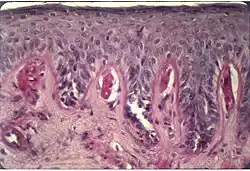

Objawy EPP wynikają z gromadzenia nadmiernych ilości protoporfiryn w tkankach. Cząsteczka protoporfiryny absorbuje promieniowanie świetlne w zakresie fal 320–595 nm; dostarczona energia powoduje przejście cząsteczki tlenu w stan tripletowy. Konsekwencją tego jest powstanie reaktywnych form tlenu, działających niszcząco na tkanki[10]. Cząsteczka protoporfiryny jest hydrofobna (lipofilna), stąd kumuluje się w błonach biologicznych i powoduje ich uszkodzenie w mechanizmie peroksydacji lipidów błonowych. Protoporfiryny wykazują też słabiej poznane działanie toksyczne niezależne od fototoksyczności. Trafiając w dużych stężeniach do dróg żółciowych tworzą złogi, zmniejszają zdolność wątroby do produkcji żółci, powodują włóknienie i marskość wątroby. W hepatocytach obserwuje się charakterystyczne dwójłomne kryształy o kształcie krzyży maltańskich. Kanaliki żółciowe są niekiedy poszerzone i mogą zawierać amorficzne złogi w swoim świetle[11].

EPP charakteryzuje się objawami skórnymi, z natychmiastową nadwrażliwością na światło przebiegającą z rumieniem i obrzękiem, niekiedy z wybroczynami krwotocznymi, połączonymi z dolegliwościami bólowymi (kłucie, pieczenie, mrowienie); z reguły nie powstają pęcherzyki ani pęcherze. Najczęściej zmiany występują na twarzy i dłoniach, ale każda odsłonięta powierzchnia skóry może być zmieniona chorobowo. Nasilenie i czas trwania objawów zależy od czasu ekspozycji na światło słoneczne. Mogą powstać przewlekłe zmiany skórne, pogrubienie skóry, hiperkeratoza (zwykle na twarzy i grzbietach dłoni). Opisywano zmiany paznokci (fotoonycholiza)[17][18]. Nie stwierdza się innych przewlekłych zmian skórnych, spotykanych w innych porfiriach: prosaków, hiperpigmentacji, hipertrichozy. Opisywano sezonowy rogowiec dłoni u pacjentów z autosomalną recesywną postacią EPP[8].